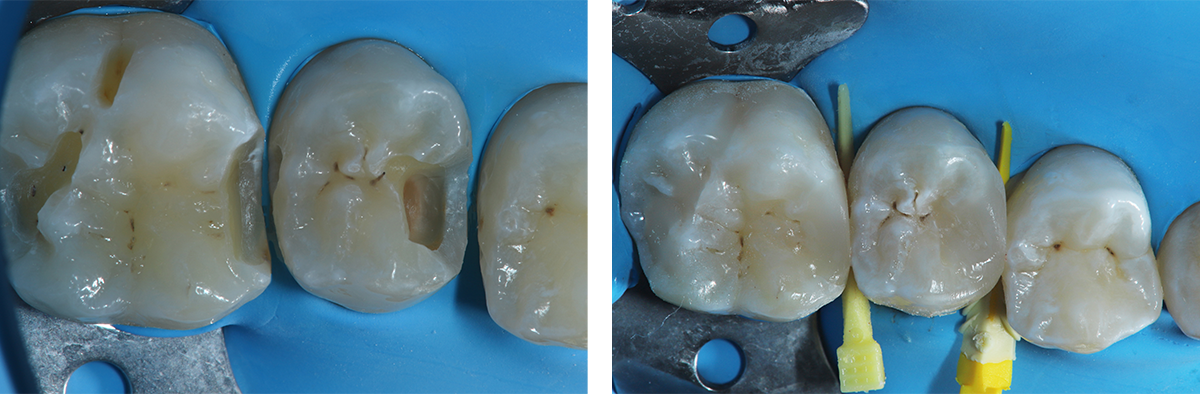

La corretta selezione dei cunei interdentali in odontoiatria restaurativa è fondamentale per la precisione ed il successo a lungo termine del restauro. Infatti, i cunei sono strumenti essenziali nel garantire un corretto adattamento della matrice al gradino cervicale, nel ridurre la formazione di debordi, nel promuovere un’emergenza anatomica e nel contribuire alla creazione di una perfetta area di contatto.

Questo articolo esamina le funzioni biomeccaniche dei cunei e analizza i vantaggi delle soluzioni più moderne, tra cui 3D Fusion™, Strata-G™, Wedge Wands™, rispetto ai cunei tradizionali in legno.

- stabilizzano la matrice sezionale e ne garantiscono l'adattamento cervicale: fondamentale per evitare la formazione di debordi ed un'emergenza il quanto più anatomica possibile.

- Creano una distrazione ortodontica temporanea, sfruttando l'elasticità del legamento parodontale. Questo permette di costruire un'area di contatto competente e non lassa.

Al contrario, dispositivi moderni come 3D Fusion™, Strata-G™ e Wedge Wands™, sono progettati per offrire una combinazione di forza di separazione calibrata, adattamento tridimensionale ed ergonomia di inserimento. I materiali sintetici utilizzati non si deformano in modo imprevedibile e mantengono la loro forma e funzione per tutta la durata del restauro. La presenza di superfici anatomiche flessibili, come nel caso del sistema 3D Fusion™ e Strata-G™, permette un ottimale adattamento della matrice al gradino cervicale riducendo significativamente il rischio di debordi e migliora la qualità del punto di contatto. Le sistematiche 3D Fusion™ e Strata-G™ grazie alla loro morfologia sigillano in modo adattivo e tridimensionale anche in presenza di concavità radicolari. Questa tipologia di cunei trova indicazione nella quasi totalità della casistica clinica di tutti i giorni. In particolar modo risulta più semplice il restauro in presenza di gradini cervicali concavi, grazie al design e alla struttura siliconica flessibile.

I cunei 3D Fusion™ offrono potenza, controllo e precisione: hanno una maggiore capacità di separazione interdentale e mantengono la forza di separazione durante tutta la procedura. Questi cunei combinano una struttura centrale rigida con delle ali laterali morbide, che si espandono per adattarsi alla forma dello spazio interdentale, garantendo al tempo stesso ottima stabilità e adattamento gengivale. Tuttavia, rispetto

agli Strata-G, i 3D Fusion sono meno indicati negli spazi estremamente stretti, dove la loro struttura più voluminosa potrebbe rendere difficile l’inserzione o risultare troppo invasiva per i tessuti gengivali.

I cunei Strata-G™ puntano invece su morbidezza, adattabilità e protezione dei tessuti, la loro flessibilità li rende atraumatici e quindi ideali in presenza di papille delicate o spazi particolarmente angolati o limitati. La loro forma anatomica è pensata per inserirsi agevolmente negli spazi interdentali più stretti, seguendo il profilo della papilla gengivale senza comprimerla eccessivamente. Anche i cunei strata-G presentano delle alette morbide che consentono un perfetto adattamento in caso di cavità concave ed irregolari. Le migliori performance cliniche e l’integrazione sinergica si ottengono in combinazione con le matrici e gli anelli separatori (3D fusion o Strata G).

La sistematica Wedge Wands™ grazie all’impugnatura monouso favorisce un’inserzione agevolata; inoltre il materiale in plastica polimerica ad elasticità controllata e la struttura anatomica più snella rispetto alle due sistematiche precedenti, favoriscono il posizionamento in spazi inter-dentali stretti; inoltre la forma più snella semplifica la gestione dei restauri di elementi con corona clinica ridotta, dove è alto il rischio di lasciare l’impronta del cuneo sulla matrice.